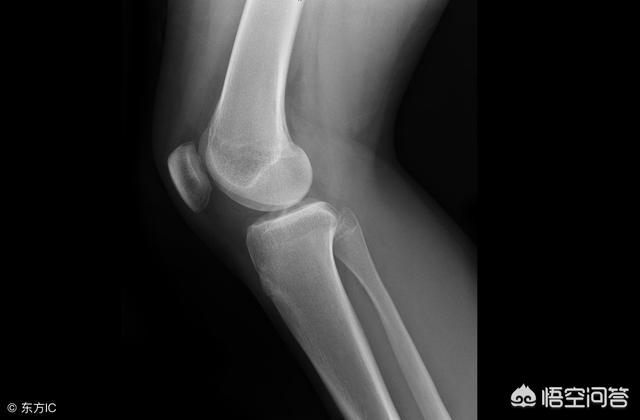

Lorsque les patients et leurs amis se rendent à l'hôpital pour un examen, la plupart du temps, le clinicien nous donne toujours les tests appropriés, certains sont bon marché, d'autres sont chers, alors en fin de compte, le test le plus cher est-il meilleur que le test le moins cher ? Les chaussures de marque sont bonnes, mais elles doivent être à la bonne taille ! Voyons comment les patients souffrant d'arthrite du genou doivent choisir leurs examens lorsqu'ils se rendent à l'hôpital.

1. L'imagerie avancée est le moyen de diagnostiquer l'arthrite.

Avec le développement de l'imagerie, le "statut" passé des rayons X en noir et blanc a été progressivement occupé par des tests d'imagerie avancés de plus en plus coûteux, tels que la tomodensitométrie et l'IRM (imagerie par résonance magnétique) et d'autres grands frères.

De nombreuses personnes souffrant d'arthrite sont superstitieuses et pensent que plus l'examen est coûteux, mieux c'est, estimant que les résultats des examens par tomodensitométrie et par IRM sont plus précis que ceux des radiographies.

Pour diagnostiquer l'arthrose du genou, des radiographies ordinaires suffisent et des examens tels que le scanner et l'IRM ne sont généralement pas nécessaires.

Contrairement au cerveau, au foie, aux poumons et à d'autres organes, le genou est une structure que l'on peut toucher à la surface du corps, il n'est pas entouré d'autres organes et tissus, et les rayons X permettent de très bien visualiser l'os !

Par conséquent, une simple radiographie, associée à un examen manipulatif effectué par un chirurgien orthopédique expérimenté, suffit généralement à diagnostiquer si un patient souffre d'arthrose !

Chez les patients souffrant d'arthrose du genou, les principales manifestations observées sur les radiographies sont le rétrécissement de l'espace articulaire du genou, l'ostéosclérose sous-chondrale et/ou la dégénérescence kystique, et la formation d'encombrements osseux sur les bords de l'articulation.

2. les examens par résonance magnétique (IRM) sont moins couramment utilisés !

Si le patient a des antécédents de traumatisme, ou si le médecin soupçonne que le patient souffre de déchirures des ligaments articulaires, de lésions du ménisque ou d'autres affections de ce type, il lui sera conseillé de subir une imagerie par résonance magnétique (IRM). L'IRM peut également être utilisée pour exclure les tumeurs, etc. Elle est également beaucoup plus coûteuse qu'une radiographie ordinaire, l'IRM de balayage coûtant 850++, l'IRM améliorée 1400++ et la radiographie seulement environ 120++.

Une fois que l'examen a précisé la présence de ces lésions dans la cavité articulaire, le médecin peut les traiter efficacement.